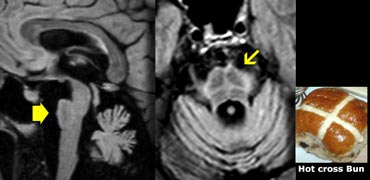

PSP with midbrain atrophy PSP with midbrain atrophy

Progressive supranuclear palsy (PSP)

PSP is also one of the atypical parkinsonian syndromes.

In PSP there is pronounced atrophy of the midbrain (mesencephalon), which accounts for the typical upward gaze paralysis.

PSP: 'humming bird sign' due to midbrain atrophy PSP: 'humming bird sign' due to midbrain atrophy

Normally the upper border of the midbrain is convex.

The atrophy of the midbrain in PSP results in a concave upper border of the midbrain with the typical 'humming bird sign' (figure).

'Hot cross bun sign' in MSA 'Hot cross bun sign' in MSA

Multi System Atrophy (MSA)

MSA is also one of the atypical parkinsonian syndromes.

MSA is a rare neurological disorder characterized by a combination of parkinsonism, cerebellar and pyramidal signs, and autonomic dysfunction.

MSA can be classified as MSA-C, MSA-P or MSA-A.

In MSA-C (formerly known as sporadic olivopontocerebellar atrophy or sOPCA) the cerebellar symptoms predominate, whereas in MSA-P the parkinsonian symptoms dominate (MSA-P was formerly known as striatonigral degeneration).

MSA-A is the form in which autonomic dysfunction predominates and is the new term for what was formerly known as Shy-Drager syndrome.

In MSA there is pronounced cerebellar atrophy and severe atrophy of the pons.

In MSA-P: low T2 SI dorsolateral putamen and slit-like increased SI lateral to putamen on T2.

In contrast to PSP, we don't see the humming bird sign, because the midbrain has a normal convex upper border.

The so-called 'hot cross bun sign', which is a result of pontine hyperintensity, is typical for MSA-C.